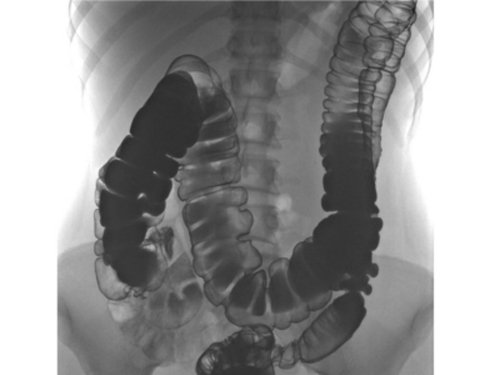

Ирригоскопия: Подготовка удовлетворительная. Ретроградно заполнены все отделы толстой кишки до уровня купола слепой кишки. начале исследования заброс в тонкую кишку контрастного вещества не получен. Отмечается общее удлинение всех отделов толстой кишки. Аппендикулярный отросток не контрастировался. Поперечноободочная кишка расположена в малом тазу. В момент контрастирования определялось спазмирование сигмовидной кишки. Контуры кишки достаточно четкие. Гаустрация выражена удовлетворительно. После опорожнения определяется значительное количество контрастного вещества в области поперечноободочной, восходящей, слепой кишки. Заброс контрастного вещества в тонкую кишку получен. при раздувании стенки кишки эластичные, в том числе в области купола слепой кишки, дополнительных образований, сужений просвета не определяется. Заключение: Долихоколон. Трансверзоптоз. Признаки гипомоторной дискенезии толстой кишки.

- ирригоскопия – рентгенологическое исследование кишечника с введением контраста – наиболее информативный метод диагностики; позволяет определить градус опускания органа;